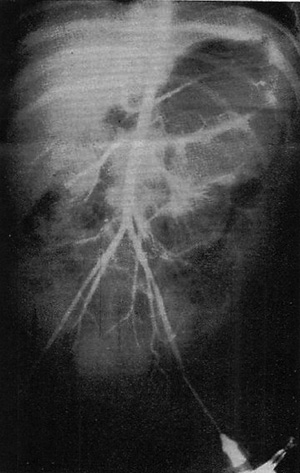

図2. 経腰的大動脈造影の合併症(血管外漏出)

【要旨】大動脈の直接穿刺による経腰的大動脈造影14,550例の合併症を分析した.重症合併症7例(0.05%),致死的合併症2例(0.014%)で,致死例の内訳は穿刺高位誤認による血胸,造影剤アナフィラキシー反応各1例で,大腿動脈カテーテル法に比較すると合併症はむしろ少なく,十分な注意を払って施行すれば,簡単,安全な検査である(図2).

【解説】 大動脈直接穿刺の方が大腿動脈カテーテル法よりもむしろ安全という結論である.しかしいかに安全と言われても,やはり侵襲の大きな検査であることには変わりなく,これ以降,Seldinger法による選択的血管造影が急速に普及し,経腰的大動脈造影は過去の検査となったが,1929年にDos Santosが開発した撮影法が到達した頂点を記述し,初期の血管造影を総括したという意味で貴重な論文である.

著者は血管外科医であるが,1977年当時既にSeldinger法が普及し,血管造影が放射線科医により行なわれるようになりつつある状況を嘆き,術前検査は主治医である外科医が行なうべきであると主張しており,論文の最後に追加されている討論でもこれを支持する意見が並んでいる点も興味深い.